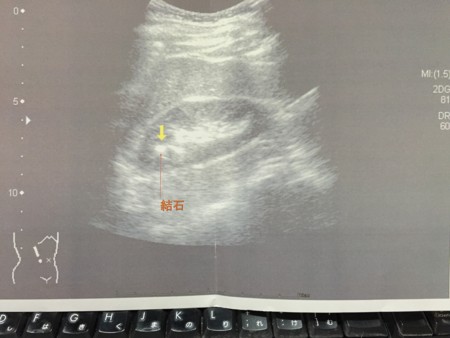

なんと、今年は、腎臓の石が少し大きく成長したらしい。去年も、石があることは伝えられていたが、今回は、わざわざ、超音波写真と腎臓結石の説明がプリントアウトされており、それをおみやげにもって帰ってくださいとおっしゃる。

そいつが何センチだったか、もう忘れてしまったが、それが腎臓から降りてくるかもしれないという。

で、先生がおっしゃるには、その写真と説明書を持っておいて、激しい痛みが背中に来たら、石のせいだとおもってください、と。

とりあえず、写真を『なんでもノート』に挟んでおいたようが良いことはわかった。